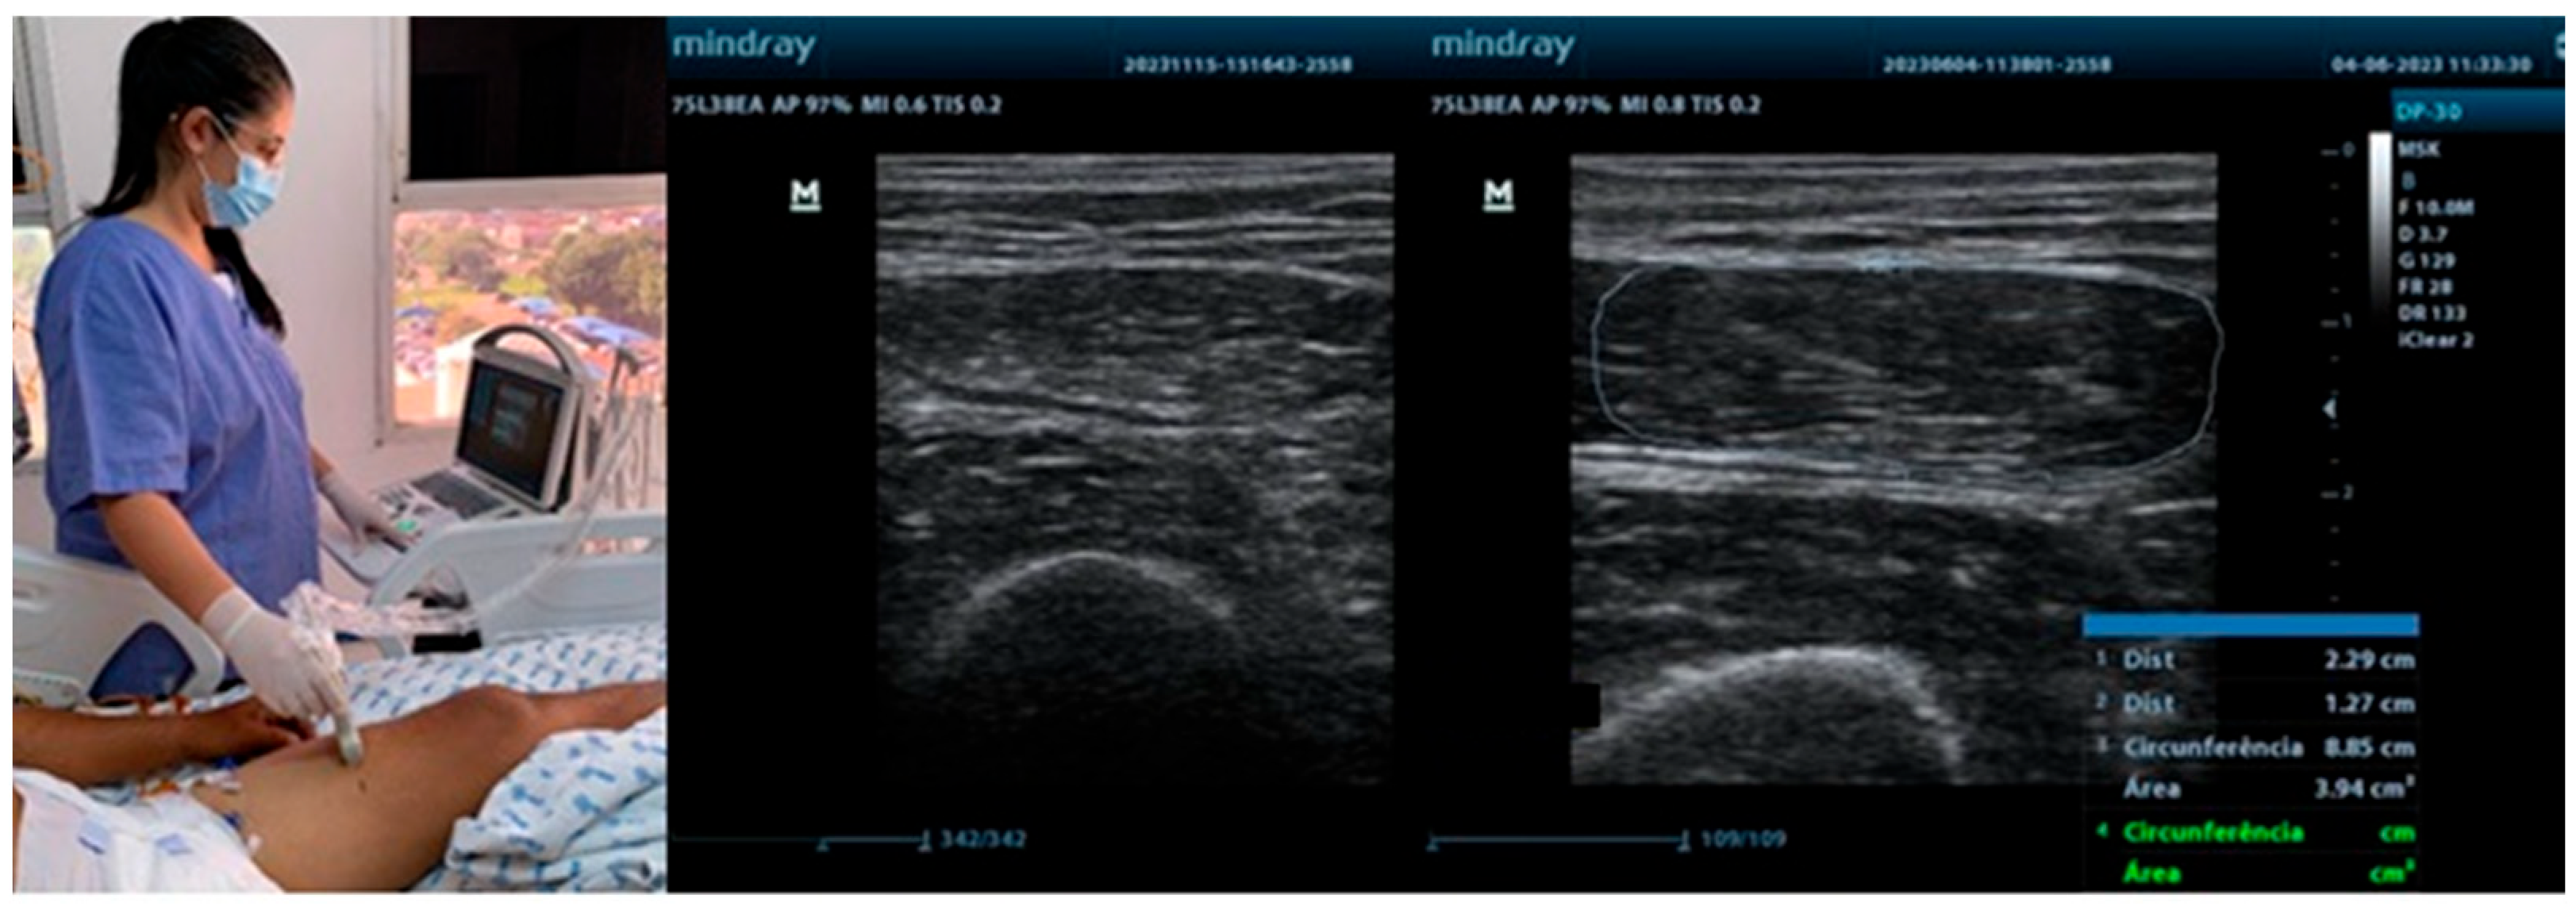

The quadriceps femoris, rectus femoris, and biceps brachii muscles are among the most frequently assessed sites in ICU patients. Their selection is primarily due to their easy accessibility for ultrasonography, their key role in mobility and overall functional performance, and their high sensitivity to the deleterious effects of immobilization and critical illness. The quadriceps femoris and rectus femoris muscles are essential for lower-limb strength, gait, and the ability to perform activities of daily living. Differently, the biceps brachii muscle provides insight into upper-limb function and overall muscular health. Evaluating these muscles enables the healthcare team to monitor both upper- and lower-limb status, offering a comprehensive assessment of peripheral muscle changes throughout hospitalization [9,10]. Figure 1 illustrates the use of ultrasound in neurocritical patients in the ICU, emphasizing aspects of muscle thickness, cross-sectional area, and echogenicity of peripheral muscles.

Figure 1. Ultrasound assessment in the ICU.